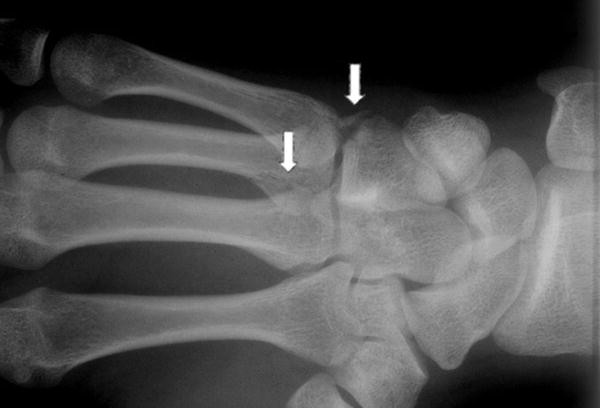

45+ Hamate Bone Fracture Treatment PNG. The hamate bone is a triangular bone located in the distal carpal row situated on the ulnar side of the hand. Just like any other bone in the body, the carpal bones can be fractured when they experience abnormal stress or trauma.

What is a bone fracture? Bone fracture is a condition where bone breaks down due to an accident, injury or excessive force. The hamate is an irregularly shaped carpal bone found within the hand.

Bone fracture is a condition where bone breaks down due to an accident, injury or excessive force. Hamate fractures are uncommon compared with scaphoid and distal radius fractures but, like these, often occur from a fall onto an outstretched hand.this topic w. A splint or cast that prevents movement is usually all that is needed unless there are other parts of the leg that are also injured. The most common treatment, especially for an athlete, is to surgically remove the broken hook of the hamate.